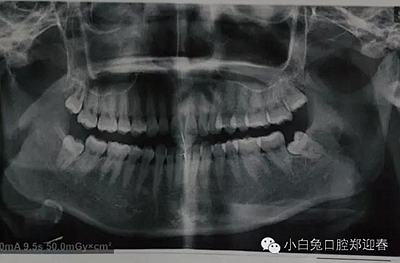

患者19歲,四顆智齒,日前,專門從西安趕過來要求智齒拔除,檢查發(fā)現(xiàn),18、38、48均未萌出,僅28萌出一頰尖,全口曲面顯示,38近中埋伏阻生,牙根瀕臨下頜神經(jīng)管,擬計劃,局麻下分兩次給予四顆智齒拔除。